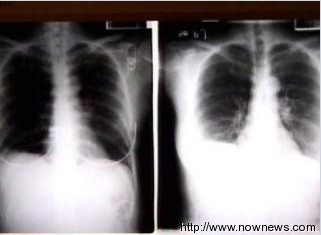

这名年轻男子靠叶克膜救回痊愈引起医界关注,因为甲型流感病毒主要侵犯肺脏,引发严重病毒性肺炎,但这名男子心脏及肾脏却也同时衰竭,心跳一度停止、肾功能急速下降甚至需紧急洗肾,这样的病情机转,就连医界也还没找到确切原因。

台大心脏外科医师王植贤表示,叶克膜并无治疗作用,主要是协助支持心肺衰竭病患能暂时休养,藉由体外循环的作用让器官做自我修复,待一周后心肺功能回稳,就可以拆除叶克膜。而这名康复返家的病患肺脏有5成受损,但肺功能仍有希望持续进步,但叶克膜治疗痊愈的案例全球相当罕见。